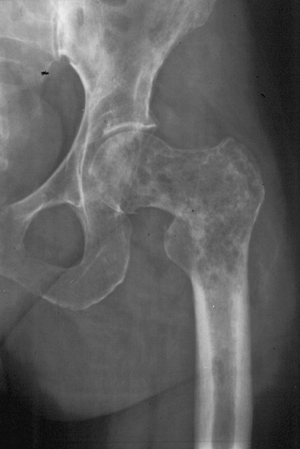

Figure 1-9

Border types. The interface at the edge of any given bone lesion on

plain radiographs may be classified as geographic, moth-eaten, or

permeative. A geographic border, as illustrated by the proximal humeral

tumor on the left, has a very narrow zone of transition (able to be

traced with a pencil-thin line) between normal and abnormal bone and

usually represents an indolent benign process, such as a unicameral

bone cyst. A moth-eaten border, as illustrated by the distal femoral

tumor in the center, has a slightly blurred zone of transition

(typically a few millimeters) and may reflect a more active process,

such as a giant cell tumor of bone. A permeative border, as illustrated

by the proximal femoral diaphyseal tumor on the right, is typified by a

broad zone of transition (usually 1 cm or greater) and usually

represents a more aggressive process, such as a sarcoma or metastatic

carcinoma. These border types are only one piece of the radiographic

interpretation, and they cannot be relied upon wholly to determine

biologic activity.